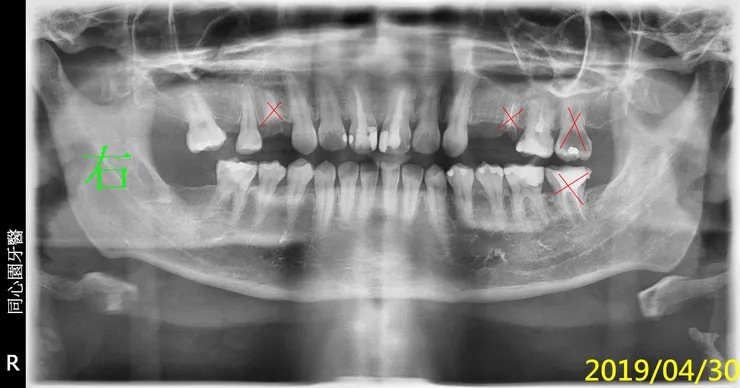

紅圈是非拔不可的牙齒,蛀到剩殘根(R.R.),這部分比較沒有異議。 牙齒殘根為何一定要拔?不拔會怎樣嗎? 我想很多人會有疑問,所以我問了M$的Copilot,AI的回答如下(令人汗顏,整理的真好,所以我直接複製貼上引用).... 本文的重點我想放在模擬治療計畫,順便說說智齒矯正取代。

我忘了這位病人後來是否有來做後續的治療,我猜應該是沒有,因為我沒印象。但我那時都已經幫他精心劃好治療計畫的圖(方便他理解龐大的工程,對,這就像預售屋之類的藍圖)。

就不浪費了,剛拿來紙上談兵,模擬計畫,what if一下。